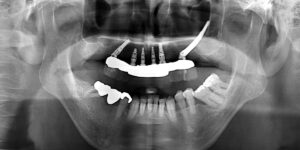

上顎左上シングルザイゴマ、5本インプラント埋入 「ザイゴマインプラント治療」を行われた患者さまのビフォーアフターをご紹介します。 ※ご紹介している症例は、あくまでも患者様固有の症例ですので、実際には患者様によって治療期間 […]